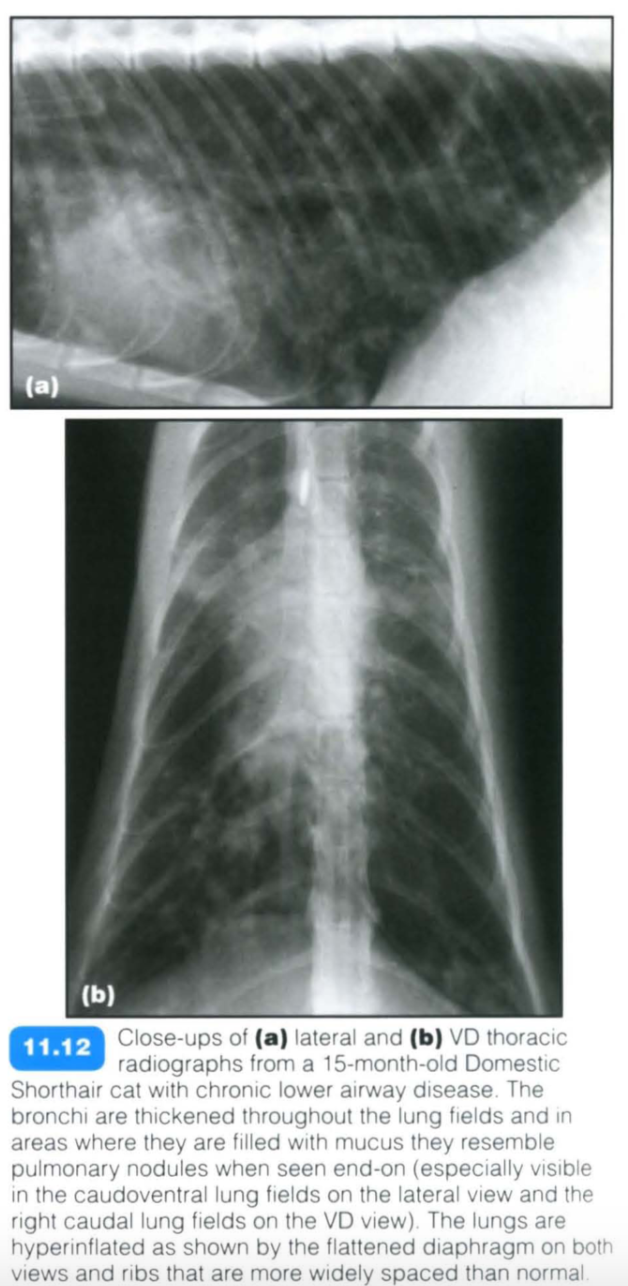

Feline chronic lower airway disease

Feline chronic lower airway disease encompasses a multitude of small airway diseases in the cat including feline asthma. Inflammation of the airways leads to a reversible obstruction to airflow (functional obstruction) and hence air trapping. The obstruction is due to a combination of bronchoconstriction, bronchial wall oedema and submucosal gland hypertrophy.

Clinical signs vary from chronic coughing and wheezing to severe respiratory distress. The condition can affect cats of any age with Siamese appearing to have an increased incidence . Hyper-responsive airways and reversible airflow obstruction lead to a reduced airway diameter and increased airway resistance. The condition can be extremely severe in presentation and care should be taken when handling dyspnoeic cats.